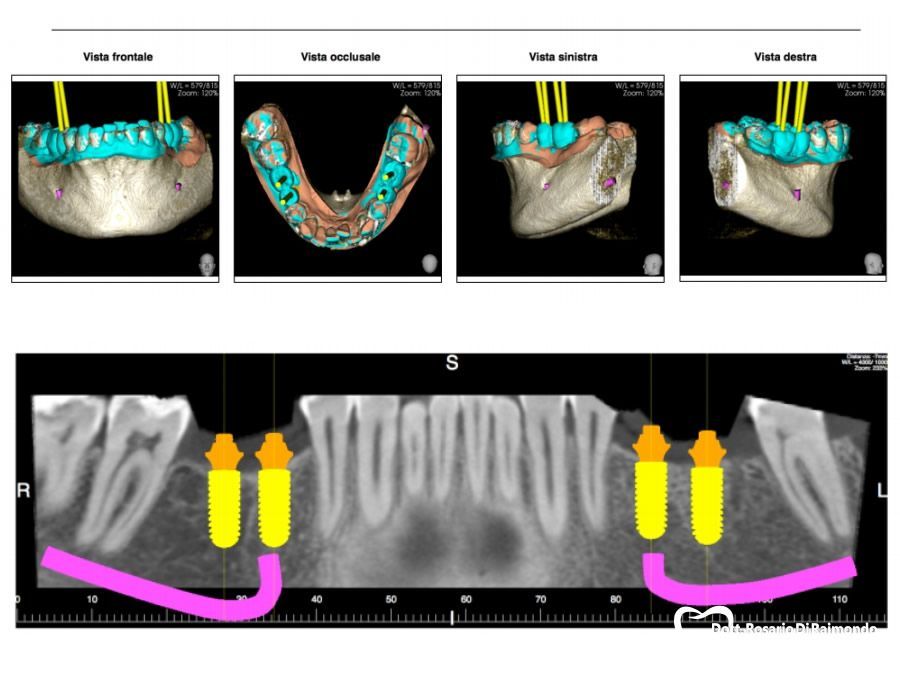

Per quanto riguarda gli “step” da seguire per l’inserimento degli impianti dentali, questi dipendono sia dalla tecnica chirurgica scelta, ma anche dalla lunghezza e diametro dell’impianto da utilizzare. Tuttavia, in linea generale i passaggi da seguire consistono innanzitutto in una pianificazione dettagliata del caso attraverso l’utilizzo di radiografie tridimensionali (TAC e CBCT) che permettono di valutare in maniera specifica e chiara la disponibilità ossea (spessore e altezza) del paziente nel sito prescelto, e successivamente nell’utilizzo di una successione di poche frese in ordine crescente all’interno dell’osso che permettono di preparare il sito per il futuro impianto dentale.

La metodica AOF, già collaudata da diversi anni, consente di ridurre il numero degli impianti necessari alla riabilitazione di un paziente totalmente edentulo, sfruttando l'osso residuo dei mascellari e con l’inserimento di quattro impianti, dei quali i due alle estremità sono inseriti in maniera inclinata (definiti tilted), grazie ad una attenta programmazione del caso clinico, con l’ausilio di software dedicati. Con questa tecnica è quindi possibile ridurre il numero degli impianti (e quindi i costi) e il “timing operatorio”, in modo tale da rendere più tollerabile l’intervento in pazienti ansiosi o anziani.

Quando parliamo di chirurgia guidata o implantologia guidata, facciamo riferimento a tecniche “flapless”, quindi minimamente invasive, nelle quali attraverso le nuove tecnologie di pianificazione chirurgica, associando i dati dell'impronta digitale del paziente con le corrispondenti sezioni della radiologia 3D (TAC o CBCT), è possibile non solo programmare con estrema precisione gli interventi chirurgici, ma anche ridurre se non addirittura eliminare i disagi intraoperatori e post-chirurgici per il paziente che non ha nessuna limitazione funzionale nei giorni successivi.

Casi Trattati

Di seguito riportiamo alcune fotografie di casi di Implantologia già trattati.